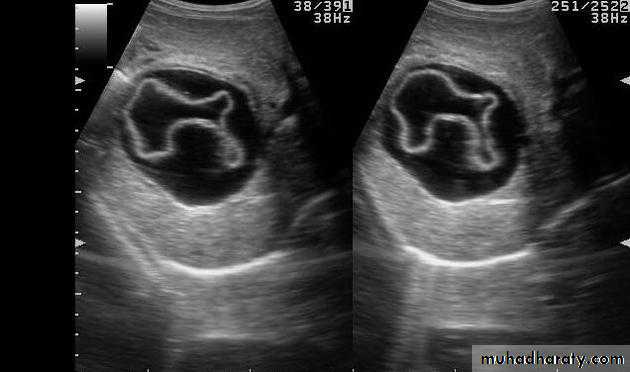

• no contrast.Gall stone & cholecystitis

Obstructive jaundice

US